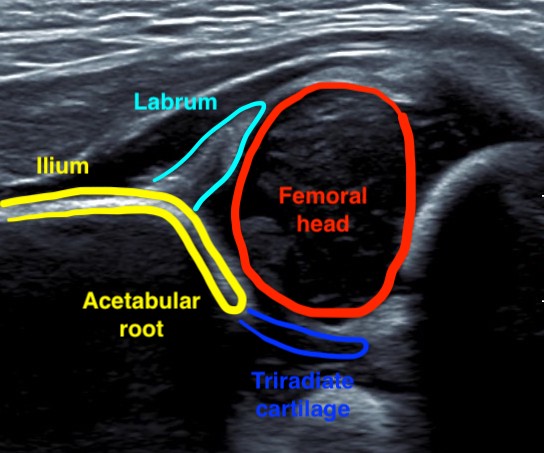

Ultrasound

Background

Best imaging before 4 - 6 months when superior femoral epiphysis cartilaginous

| Alpha Angle | Beta Angle | Dynamic |

|---|---|---|

|

Between ilium & bony roof acetabulum

Between ilium & cartilage roof / labrum

Ultrasound Ortolani / Barlow

Normal > 60°

The lower the alpha angle, the more subluxed the hip is

Normal < 60o |

Alpha angle between ilium and bony roof of acetabulum

Beta angle between ilium and cartilage roof / labrum